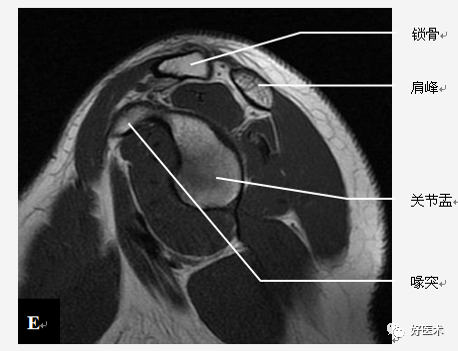

肩关节骨骼构成

三块骨:肩胛骨、锁骨、肱骨

两个关节:

肩锁关节

盂肱关节